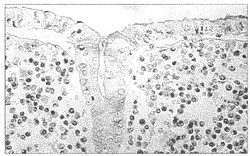

全结肠息肉状浆细胞型淋巴肉瘤1例

短篇及病例报告

患者女性 ......